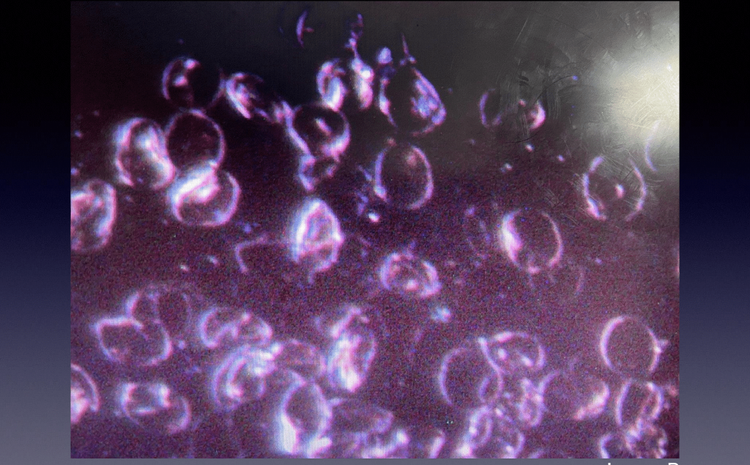

Post-Metadichol

Twenty-three minutes after taking Metadichol, the red blood cells are suddenly free to move independently, with the resulting optimal surface area now visible. Also, note the COMPLETE absence of oxidative stress in the background, which could not be found anywhere in the second blood sample.

The patient was shocked as she watched this change, exclaiming that she had never seen anything act this fast or thoroughly.